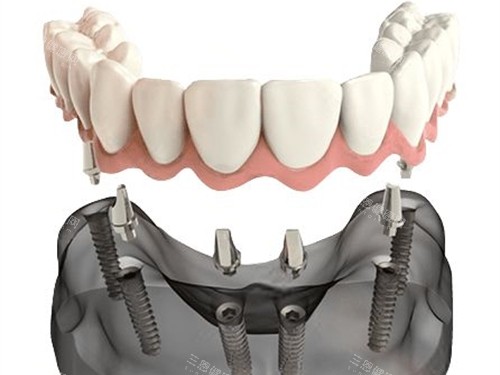

半口种植牙联排牙冠安装示意图